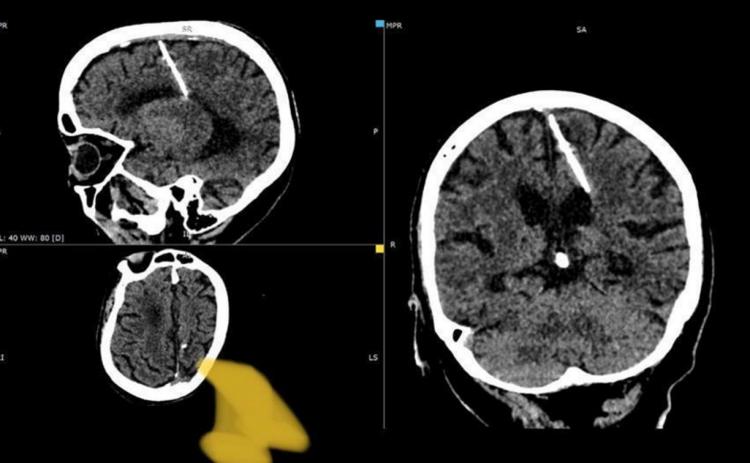

С невероятным и от части грустным случаем в своей практике столкнулись сахалинские рентгенологи – в мозгу 80-летней пациентки они обнаружили трехсантиметровую иглу, сообщает astv.ru.

Из-за того, что игла проникла в левую теменную долю, гражданке удалось выжить, к тому же, наличие инородного тела в головном мозгу никак не повлияло на ее жизнь, обошлось даже без головных болей. Иглу заметили только в этом году при проведении компьютерной томографии.

В настоящее время здоровью пациентки ничего не угрожает, за ее состоянием наблюдает лечащий врач. Оперативное вмешательство было принято не проводить, так как это может только ухудшить ее состояние.